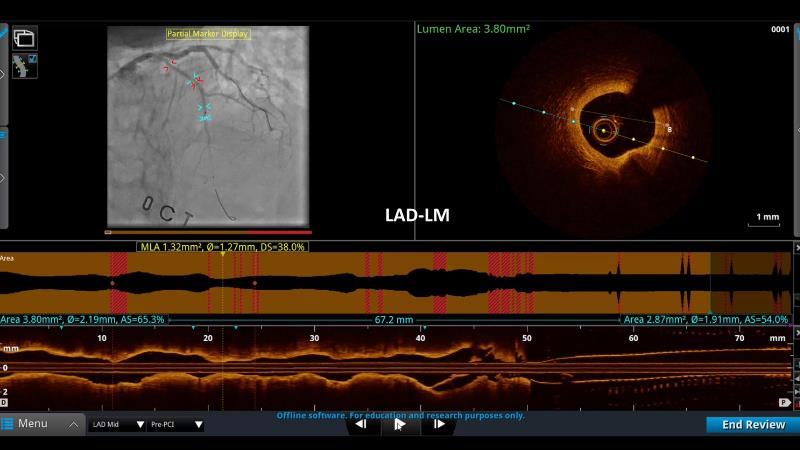

- To define the use of OCT in PCI of complex coronary lesions